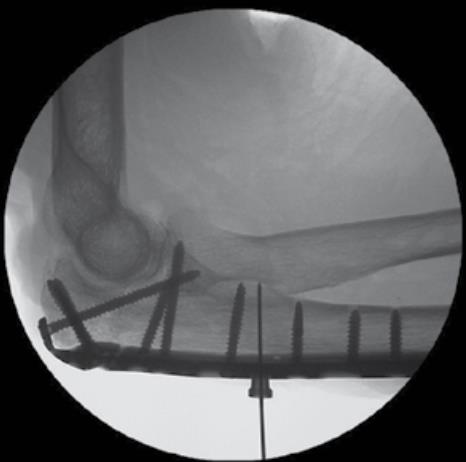

• Fracture Reduction

• reduce the fracture by levering the shaft of the plate to the distal fragment

• confirm fracture reduction and plate alignment using fluoroscopy

• Distal Fragment Fixation

• using the 2.7mm x 40mm drill bit, drill through the distal end of a FreeFix slot that is distal to the fracture line through both cortices

• this will allow for dynamic compression of the fracture

• measure screw length using the appropriate scale on the 50mm Depth Gauge, then insert a 3.5mm compression screw using the T-10 Driver while applying interfragmentary compression

• note: the depth gauge has a dual scale to reflect measurements through the PDGs (top scale) or directly through the plate (bottom scale)

• Fluoroscopic Confirmation

• repeat steps past two steps for the remaining olecranon screw hole using a 3.5mm Multi-Thread Locking Screw

• confirm proper plate positioning, fracture reduction and screw lengths using fluoroscopic imaging